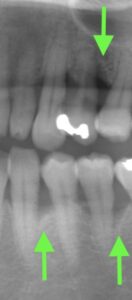

歯周病に罹患されている患者さんです。

当院に受診された際の最初のレントゲン写真です。

矢印で指している部分の骨が溶けてしまっています。

ここが歯周病が進行している部分です。

この数値が最初のレントゲン写真時の歯周ポケットの数値です。

2~3mmが健常ですから、この数値は良くないことがわかります。

ということで、歯ぐきの中の歯石を取った後はどうなったのか。

治療の前後を見てみましょう。

治療前

治療後

いかがでしょうか。

レントゲンで見ると、歯周病により一度溶けてしまった骨がまた少しずつ回復しているのがわかります。

歯周ポケット検査の数値も改善がみられました。